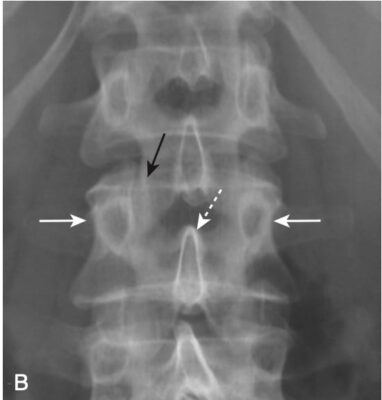

- Trong hình chiếu thẳng, mỗi thân đốt sống hiển thị hai cuống cung hình oval có thể nhìn thấy được ở hai bên của thân đốt sống. Các cuống cung của L5 thường rất khó nhìn thấy ngay cả ở những người bình thường, bởi vì độ ưỡn của cột sống thắt lưng (xem Hình 1, B).

- Trên phim chụp X quang cột sống thắt lưng thông thường ở tư thế chếch, các cấu trúc giải phẫu thường chồng lên nhau, tạo nên một hình bóng giống như phần trước của loài chó sục Scotland, dấu hiệu chú chó Scottie (Scottie dog) nổi tiếng (Hình 3).